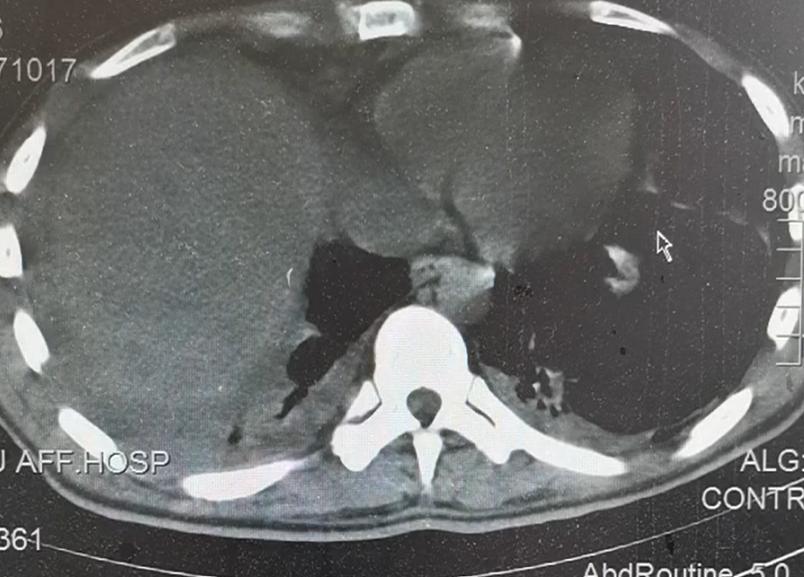

4月22日,因病情嚴(yán)重,羅某被送往遵義醫(yī)科大學(xué)附屬醫(yī)院。醫(yī)院急診科劉同英醫(yī)生說,羅某顱腦CT右側(cè)顳頂葉腦出血、右側(cè)顳頂葉腦水腫,左側(cè)肺少量液氣胸、右側(cè)肺有少量胸腔積液。此外,他的肝右葉也受到了損傷。結(jié)合檢查結(jié)果,醫(yī)生討論后認(rèn)為,羅某生活在寄生蟲感染區(qū),有疫水接觸及生吃螃蟹的情況,考慮其感染了寄生蟲。